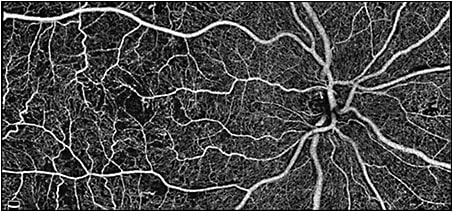

The AngioVueHD Montage feature further extends this wide field capability by automatically combining 2 high-density 6 mm x 6 mm scans — the macula and the optic disk — to provide the highest resolution imaging available in a 10 mm x 6 mm imaging format.

Optovue’s AngioVueHD increases sample density from 304x304 A scans to 400x400 A scans, which is 73% more than available previously. “This results in a 33% increase in resolution, so that physicians can see even small capillaries clearly,” Wei says. To compensate for artifact caused by eye motion during scanning, DualTrac technology employs 2 levels of tracking, 1 during scan acquisition and 1 during the post processing phase.

AngioVueHD OCTA technology is uniquely suited for patients who have retinal disease associated with changes to the vasculature, such as wet AMD and diabetic retinopathy, because it quickly provides high-resolution images of the retinal vasculature. “By providing a wider field of view along with improved resolution, physicians can see the vasculature more clearly,” Wei says. “They are also able to assess for pathology that arises in the mid periphery more easily.”

“AngioVueHD Montage software lets us view the entirety of the CNV in one image, and thereby monitor its size over time,” Dr. Waheed says. “This is also invaluable for peripapillary CNV as well as for patients with polypoidal choroidal vasculopathy whose lesions may be eccentric and therefore not captured on a 3 mm x 3 mm scan. I was using 6 mm x 6 mm scans to screen these patients, but sometimes I wasn’t confident in the results because of the low scanning density. The higher the scanning density in a wide field of view, the more confident I am in my clinical assessment.”